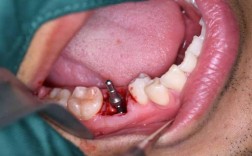

在局部麻醉下进行,步骤包括:

- 消毒、铺巾,麻醉生效后切开牙龈,分离黏骨膜,暴露牙槽骨;

- 使用种植机逐级备洞(制备适合种植体直径和深度的窝洞),植入种植体(常用纯钛材质,生物相容性佳,易与骨结合);

- 若骨量不足,可同期进行骨增量(如植入自体骨、人工骨,或使用骨引导膜引导骨再生);

- 缝合牙龈,术后拍摄X光片确认种植体位置。